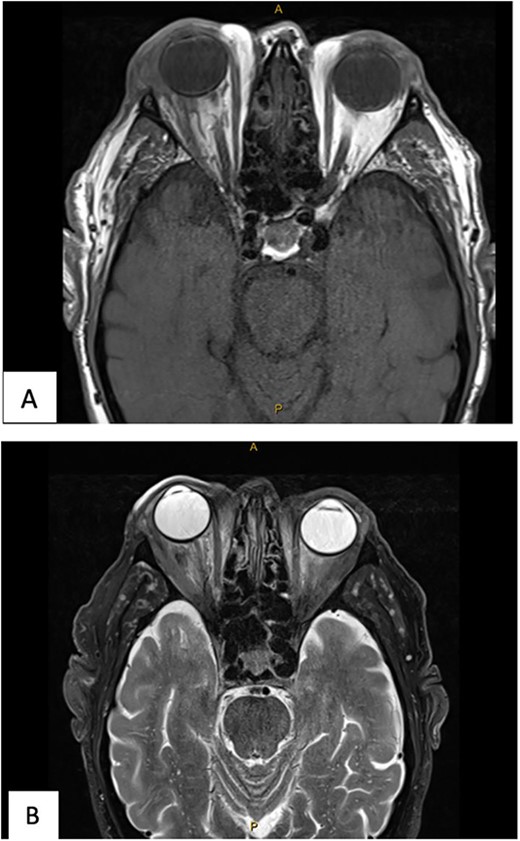

The patient underwent transconjunctival peritomy and drainage of the inferomedial abscess. However, vision regressed from hand movements to no light perception 5 days following initial drainage. Re-imaging of the orbit revealed a new retroorbital abscess accumulation superior-temporally (Fig. 4) that was also then drained. Both collections contained frank pus, and cultures also grew methicillin sensitive S. aureus, requiring a prolonged course of intravenous flucloxacillin and oral steroids. Subsequent MRI showed right lateral retroorbital abscess regression and less prominent retroorbital phlegmonous changes (Fig. 5). However, vision did not return to the patient’s eye.

(A) MR Orbit T1 TSE R TRA. (B) MR Orbit T2 FS TSE TRA. The right lateral retroorbital abscess has reduced in size. The traction on the optic nerve has reduced.